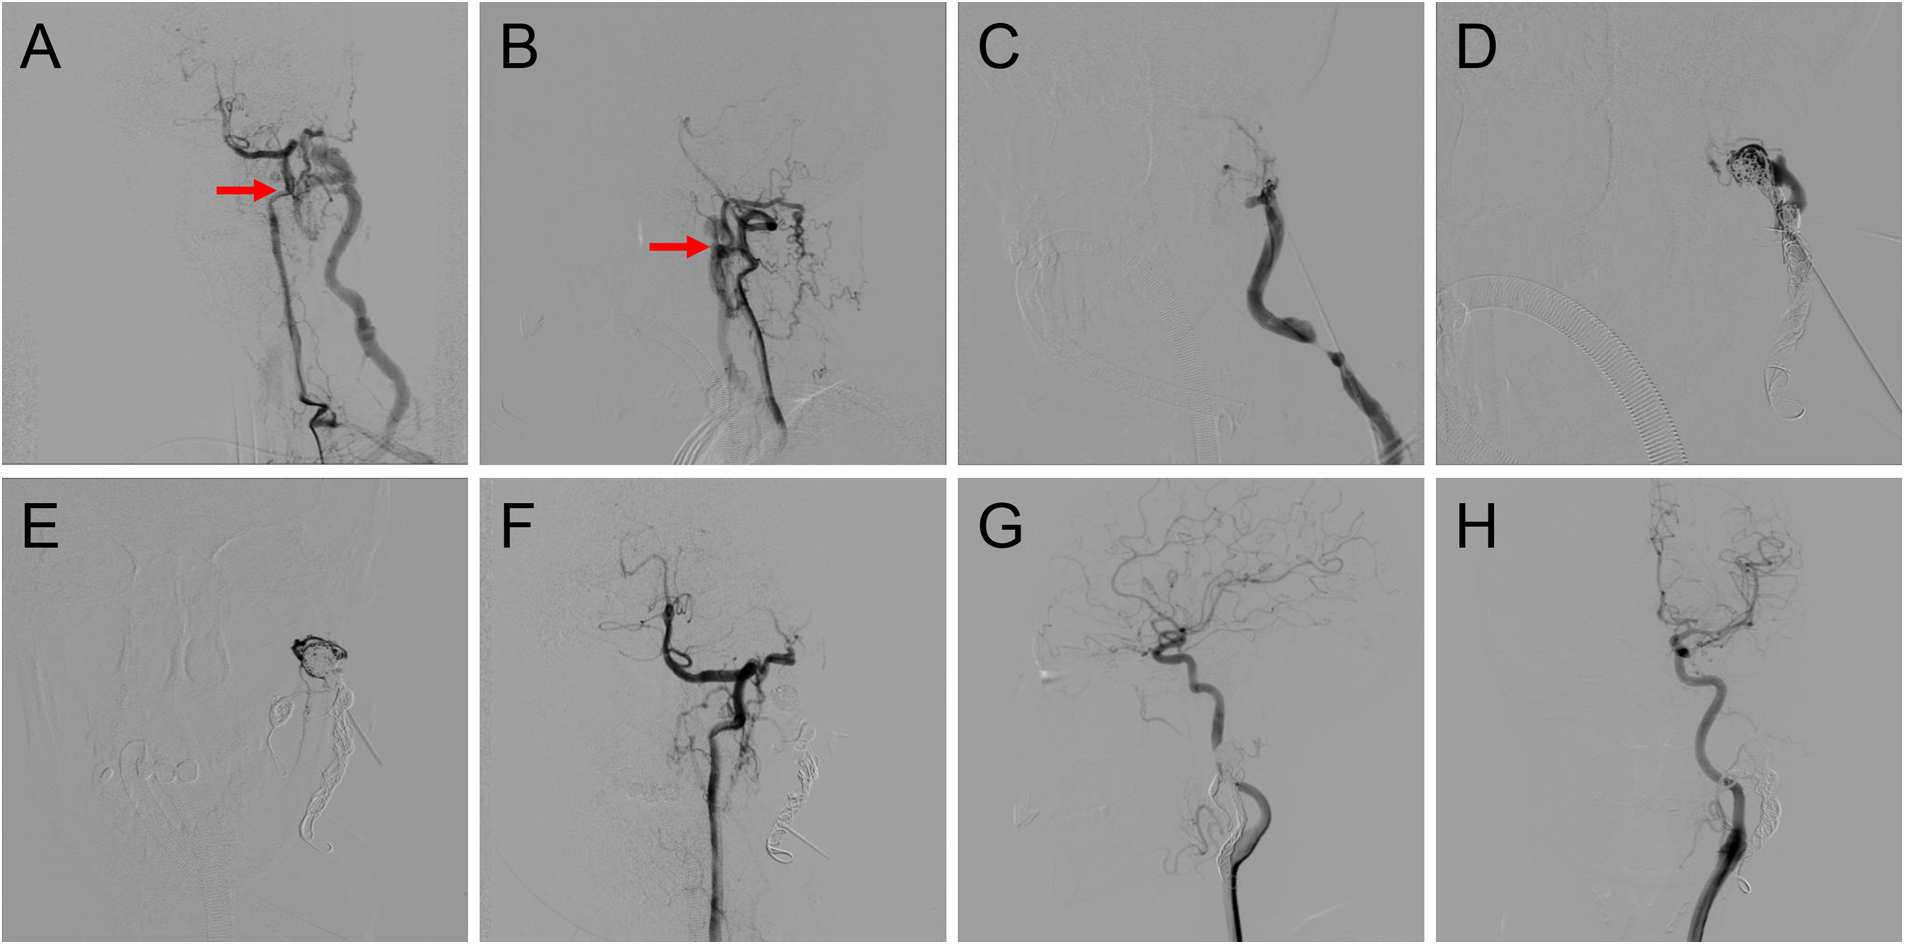

According to previous reports, ethanol embolization was initiated under general anesthesia to control pain (12). Briefly, baseline angiograms were obtained using the femoral artery approach to assess the extent and hemodynamic characteristics of TAVFs and to determine whether transarterial or direct puncture access would be used (Figures 2A,B).

Figure 2

Procedure of coil-assisted ethanol embolization of traumatic arteriovenous fistulas. (A,B) Anteroposterior and lateral views of baseline angiography. (C) Direct puncture of the nidus. (D) Configuration of coils. (E) Angiography indicating the reduction of blood flow. (F) Final angiography after ethanol injection showing 100% devascularization. (G,H) Anteroposterior and lateral views of angiography 1.5 years postoperatively. Red arrows: arteriovenous shunts.

A dominant outflowing vein (DOV) of TAVF is defined as the dilated vein originating from the nidus with the maximum and fastest flow (13). If angiography identified the DOV (Figure 2C), we penetrated directly with an 18-G puncture needle. A 2.1-F microcatheter (Asahi, Seto, Japan) was then inserted into the DOV, and venography was used to confirm the correct location of the microcatheter. Next, the three-dimensional mechanically detachable coils (Micro Therapeutics, Irvine, CA, USA) and synthetic fiber-attached stainless steel coils (Cook Medical, Bloomington, IN) were delivered via the microcatheters until repeat venography represented decreased blood flow (Figures 2D,E). For patients without a significant DOV, coils were placed in the nidus.

Absolute ethanol was injected at a dose of 0.1 ml/kg body weight per injection, with a maximum of 1 ml/kg body weight per procedure. An angiogram was performed 5–10 min after each ethanol injection to determine whether the AVFs were effectively embolized. If the nidus was still noted on angiography, repeated ethanol injections were required (Figure 2F).

Patients were followed up at regular intervals of 1–3 months after the initial treatment with physical examinations. The color duplex ultrasound or contrast-enhanced CT was performed for outpatients. Angiographic re-examination was regularly carried out during the patient's first follow-up. Angiography was also recommended if the clinical outcomes of symptoms and signs of the patients improved or worsened during long-term follow-ups (Figures 2E,F). Additional embolotherapy was required if residual fistulas were detected on angiography.